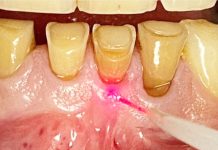

Dalle pubblicazioni del professor Tomasi con approccio multilivello, comprendiamo come la probabilità di chiusura della tasca sia notevolmente influenzata da fattori legati al dente, come la profondità di sondaggio iniziale e l’anatomia radicolare, e da fattori legati al paziente come l’età, la presenza di placca e l’abitudine al fumo (15). Conseguentemente all’introduzione del concetto di periodotal debridement si sono sviluppate tecniche di terapia non chirurgiche mininvasive definite come minimally invasive non surgical techniques (MINST). La procedura MINST si ottiene attraverso il periodontal debridement in anestesia locale, utilizzando prevalentemente strumenti ultrasonici con tips di piccole dimensioni (fig. 1) per lavorare in difetti stretti e profondi con anatomie difficili e sfruttando la magnificazione (loupes o microscopi operatori) (16).

Per massimizzare la guarigione e poter parlare di MINST è di conseguenza necessario tener presente le motivazioni biologiche che portano alla conservazione dell’architettura gengivale iniziale, creando una ferita di minima entità con una gestione delicata dei tessuti duri e molli favorente la stabilità del coagulo all’interno della ferita.

La scelta di adottare lo strumento ad ultrasuoni, in particolare quello piezoelettrico, deriva dal fatto che risulta essere lo strumento che, a parità di efficacia, irruvidisce e rimuove meno cemento radicolare rispetto alla curette (17). Per esprimere al meglio la mininvasività è necessario però conoscere adeguatamente frequenza e ampiezza di vibrazione che rappresentano dei parametri fondamentali. Nello stesso modo anche gli strumenti air-polishing (air polishing devices, APD) con polveri a bassa abrasività, come glicina ed eritritolo, giocano un ruolo importante durante le manovre di debridement. Questi strumenti sono in grado di rimuovere efficacemente il biofilm batterico con gli stessi risultati degli strumenti tradizionali, ma sicuramente con un indice di abrasività quasi nullo per i tessuti del dente e per i materiali resinosi e ceramici.